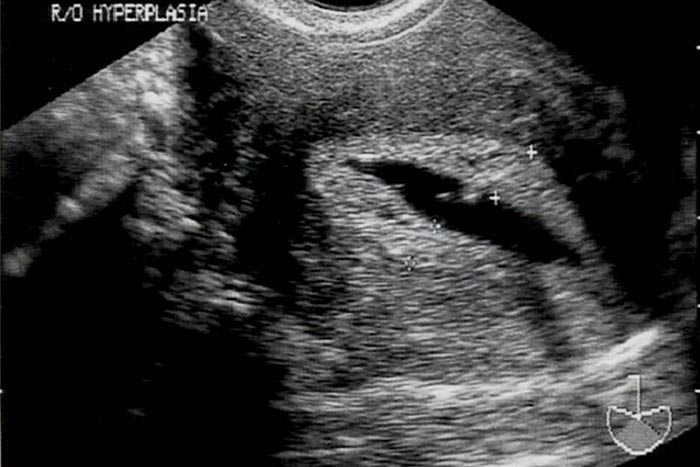

هیپرپلازی آندومتر در نتیجه پرولیفراسیون غیرطبیعی آندومتر ایجاد می شود و علت خونریزی 8-4% زنان در دوران یائسگی است. ریسک فاکتورهای ایجاد هیپرپلازی عبارتند از: مصرف استروژن بدون

پروژسترون ، مصرف تاموکسیفن ، نولی پاریتی ،چاقی ، فشارخون بالا و دیابت. (4)

اجرای هیستروسونوگرافی در روزهای 10-7 سیکل قاعدگی که جدار آندومتر نازک و منظم است در تشخیص هیپرپلازی کمک کننده است. تشخیص به موقع هیپرپلازی از این نظر که احتمال پیشرفت هیپرپلازی تا مرحله کانسر وجود دارد بسیار مهم است.

تشخیص قطعی هیپرپلازی فقط با بیوپسی امکان پذیر است.